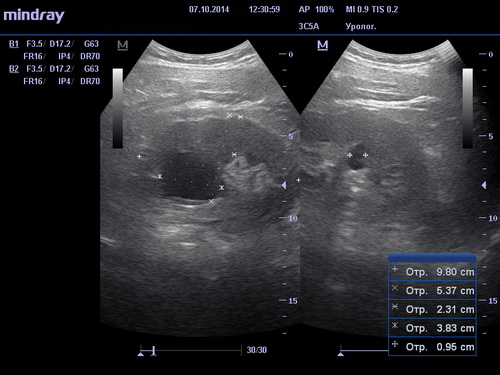

Проведение процедуры

Необходимо раздеться до пояса и лечь на кушетку. Врач, проводящий исследование нанесёт специальный гипоаллергенный гель на участки исследования для лучшего скольжения датчика и беспрепятственного прохождения ультразвуковых волн. Вся процедура занимает не более двадцати минут. Программное обеспечение позволяет создать модель работающего органа и увидеть все возможные изменения, происходящие с ним. После окончания исследования пациент получит на руки письменный результат с рекомендациями врача.

Какие заболевания может выявить УЗИ почек?

Исследование почек поможет определить и выявить следующие заболевания:

- присутствие в почечных лоханках камней или песка;

- наличие любых новообразований как доброкачественных, так и злокачественных;

- изменение чашечно-лоханочной системы;

- стеноз почечных артерий;

- изменения в сосудах почек;

- пиелонефрит на ранних стадиях.

Наши клиники проводят полное УЗИ почек в Москве с помощью самых современных технологий. Допплерографическое исследование помогает обследованию кровеносных сосудов, благодаря чему становится видны любые изменения в кровоснабжении почек. Одновременно с обследованием почек может проводиться ультразвуковое обследование мочевого пузыря для выстраивания полной картины работы мочеполовой системы пациента.